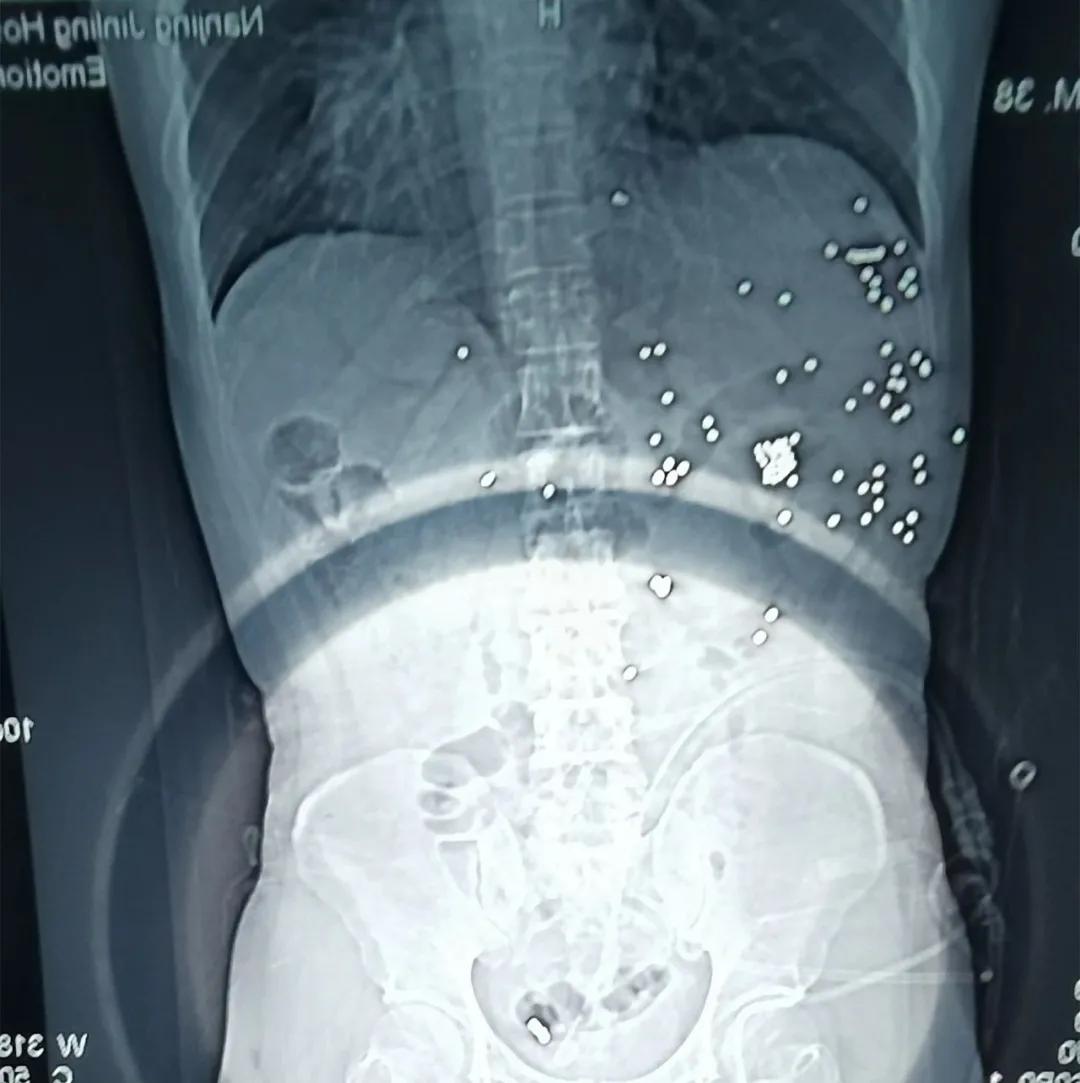

不知,你还记得那张腹腔残留着几十颗*弹霰**铁砂的X光片吗?

还记得那张腹腔残留着几十颗*弹霰**铁砂的X光片吗?片子的“主人”,是台州路桥公安分局的辅警林新志。

于是,一场由肝胆外科、血管、胃肠、创伤外科专家组成的多学科手术在凌晨的手术室里紧张地进行着。打开腹腔后,杨鹏发现林新志的肝部、胃部、胰腺、肠道被*弹子**打伤,近百颗*弹霰**铁砂“侵入”腹腔,在对肝部进行清创后,又是一小时的肝部压迫性止血。探查大血管不再出血后,其他学科团队马上有条不紊地进行手术。当天上午8点30分钟,手术结束。林新志的命暂时保住了,但他体内仍留着近百颗铁砂,胃、小肠、肝脏、胰腺等多个脏器受到重创,血色素也不到常人的三分之一,随时又会陷入危险。

只是,那八九十颗残留在体内的*弹霰**铁砂,或将和他度过余生。